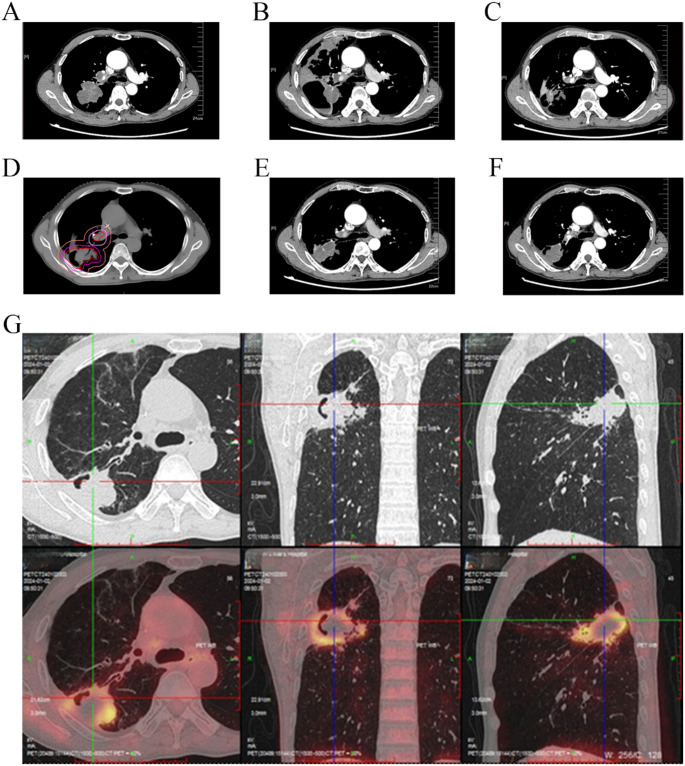

背景:smarca4缺陷未分化胸椎肿瘤(SMARCA4-UT)是一种罕见的高侵袭性恶性肿瘤,其特点是早期远处转移,预后差,中位总生存期(OS)仅为4-7个月。传统的治疗方法提供有限的益处,而新的数据表明联合免疫治疗、化疗和抗血管生成方法的疗效。我们报告一例52岁男性重度吸烟史,表现为意识丧失和肢体抽搐。影像学显示脑转移和胸部肿瘤。在手术切除脑病变和肺活检后,患者被诊断为SMARCA4-UT,无可靶向的驱动突变和程序性死亡-配体1 (PD-L1)肿瘤比例评分(TPS)结论:综合化疗免疫治疗、抗血管生成、巩固放疗和挽救性手术的多模式治疗可使SMARCA4-UT脑转移患者持久生存。它强调了结合全身和局部治疗的潜力,为管理这种具有挑战性的疾病提供了有价值的见解。

Background: SMARCA4-deficient undifferentiated thoracic tumor (SMARCA4-UT) is a rare and highly aggressive malignancy characterized by early distant metastasis and a poor prognosis, with a median overall survival (OS) of only 4-7 months. Traditional therapies offer limited benefit, while emerging data suggest the efficacy of combined immunotherapy, chemotherapy, and anti-angiogenic approaches. We report a case of a 52-year-old male with a heavy smoking history who presented with loss of consciousness and limb convulsions. Imaging revealed brain metastasis and a thoracic tumor. After surgical removal of the brain lesion and a lung biopsy, the patient was diagnosed with SMARCA4-UT, showing no targetable driver mutations and a programmed death-ligand 1 (PD-L1) tumor proportion score (TPS) < 1%. The patient underwent first-line treatment with tislelizumab, bevacizumab, carboplatin, and paclitaxel. Despite discontinuation of bevacizumab due to a tumor cavity, the patient achieved partial remission (PR) after six cycles. Notably, consolidative thoracic radiotherapy (TRT) was administered following systemic disease control to enhance local control. After 5 months of maintenance therapy, oligoprogression of the primary lung lesion was detected and the progression-free survival (PFS) of first-line treatment reached 14 months. The patient then performed salvage surgery for local lesion and continued with maintenance treatment. As of May 2025, the patient has survived for 31 months since the initial diagnosis.

Conclusion: Multimodal therapy integrating chemoimmunotherapy, anti-angiogenesis, consolidative radiotherapy, and salvage surgery achieved durable survival in SMARCA4-UT with brain metastasis. It highlights the potential of combining systemic and local therapies, providing valuable insights for managing this challenging disease.